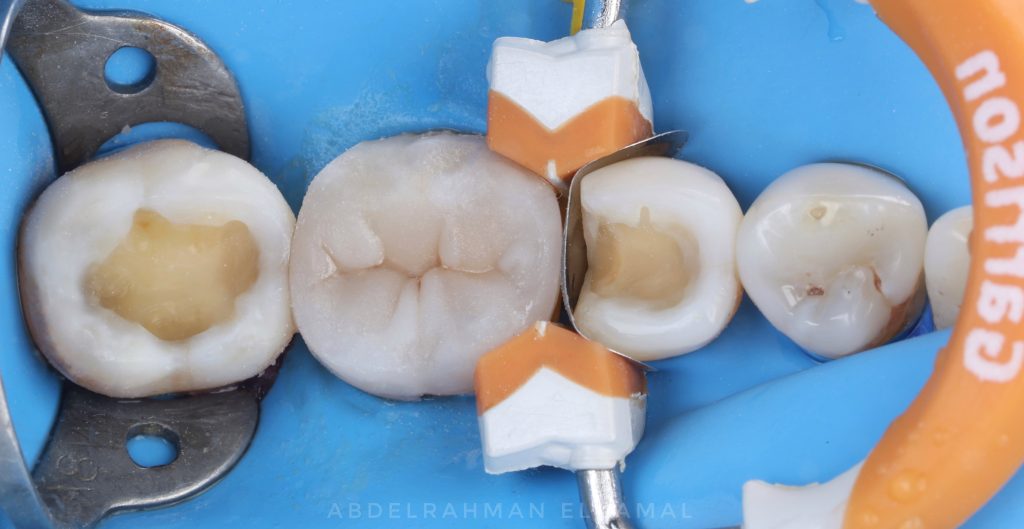

pre operative picture shown old defective restoration & recurrent Caries proximally for first molar .

second premolar & second molar with old cavities

rubberdam applied then stated caries removal using caries detector dye .

sandblasting for cavities with aluminum oxide 29 micron.

first molar built up proximally with saddle matrices then occlusaly cusp by cusp technique with simple anatomy .

then started second premolar using sectional matrix & garrison ring for separation &simple anatomy obtained . Then second molar the same way .